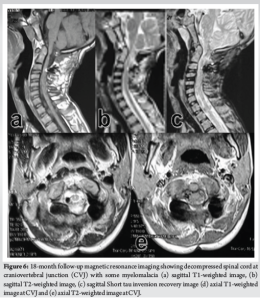

A 14-year-old boy presented to the spine clinic with progressive weakness of the bilateral upper limb, progressing to bilateral lower limb for the past 1.5 years following trivial trauma to the neck and with bowel and bladder incontinence for the past 1 year. At presentation, he was not able to stand without support, had increased tone (modified Ashworth grade 1) in bilateral upper and lower limbs, with functional motor power present and no sensory deficit in any of the dermatomes. On elicitation, both upper and lower limb reflexes were exaggerated. Exaggerated pectoralis reflex and presence of scapulohumeral reflex suggested a clinical diagnosis of supra-axial cervical myelopathy. On further evaluation, special signs such as Hoffman’s sign and grasp-release test were positive. Cervical spine radiograph showed atlantoaxial subluxation with decreased posterior atlanto-dens interval along with fusion of C2 and C3 vertebrae (Fig. 1). On magnetic resonance imaging cervical spine, thecal sac and spinal cord compression at the level of C1/C2 joint with no visible cerebrospinal fluid rim was noted (Fig. 2). 3D Computed tomography angiography (CTA) of the cervical spine showed an incomplete anterior and posterior arch of the atlas with well-corticated bony fragments within the posterior arch defect. Note of fenestration of VA on right side and high-riding VA was also made (Fig. 3). A final diagnosis of supra-axial extradural compressive cervical myelopathy due to congenital atlantoaxial subluxation with anomalous VA (Nurick Grade 5) was made. The patient was planned for C1-C2 reduction and posterior instrumented fusion using C1 lateral mass and C2 laminar screws under intraoperative neuromonitoring. The patient was positioned prone on Mayfield, and a longitudinal midline approach from C1 to C3 was carried out, elevating the paraspinal muscle subperiosteally from the midline. A congenital defect in the posterior arch of C1 was noted. First, the left side C1 lateral mass screw was put after identifying the entry point. On the right side, the aberrant VA was freed from the posterior arch of C1 and retracted, inferiorly exposing the lateral mass of C1 along with facets of C1-C2 joint, and C1 lateral mass screw was inserted. Further, laminar screws were placed bilaterally in C2. C1 was reduced over C2 using rod cantilever mechanism and by applying compression force bilaterally between the C1 lateral mass and the C2 laminar screws. Decompression was achieved by removing the remaining C1 posterior arch and corticated bony fragment from the midline. Harvested local bone autograft was placed in the C1-C2 joint on the left side and the prepared fusion bed posteriorly (Figs. 4 and 5).

Gait training was started, and post-operative neurological assessment showed normal tone in both upper and lower limbs at 6 weeks. At 6 months, the patient started walking with support and had complete recovery of bowel movements and partial recovery in bladder sensations. At final follow-up of 18 months, the patient is walking independently (Nurick Grade 2). The patient has returned to his routine daily activities with no motor deficit in bilateral upper and lower limbs (Fig. 6).